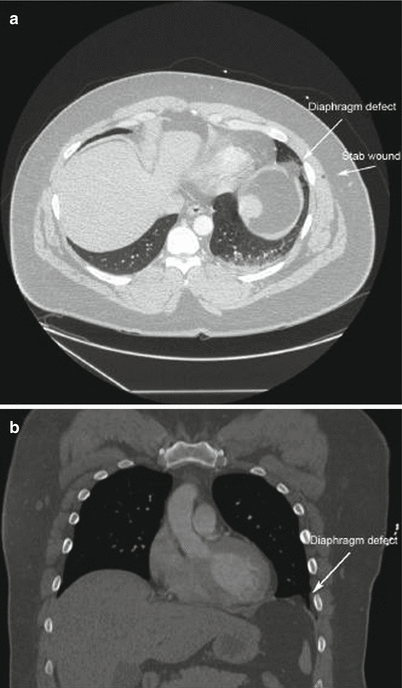

Fig. 16.5

(a) Stab wound to the left chest with evidence of diaphragm injury adjacent to wound tract. (b) Coronal reconstruction of diaphragm injury showing herniation of abdominal fat through defect

One area where newer generation CT scans have become useful is the detection of diaphragm injuries. New multidetector CT scanners can now resolve the presence of diaphragm injuries with a sensitivity and specificity of 82–94 % and 88–95.9 % with an overall accuracy of almost 96 % and negative predictive value of 93 %. While this represents a significant improvement from the older technology scanners, a high index of suspicion remains important as significant injuries can still be missed by imaging alone.